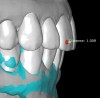

3. The face scan coupled with an optical scan or scanned impressions/casts, which are used to mock-up the desired restorative result by using a modeling software. This allows for creation of digital wax-ups and restoration designs, comparison of pre/post-restoration contours and positions using transparent overlays (permitting viewing of the anticipated changes relative to baseline through the use of 3D superimposition), and anticipation of endodontic procedures that may be required due to the expected reduction of tooth structure needed to achieve the desired outcome without altering tooth positions (Figure 8 and Figure 9). In turn, multiple try-ins and adjustments resulting from insufficient information are either entirely avoided or minimized. This detailed information is almost impossible to visualize using stone models. Also, it reduces working time in the design phase and "virtually" archives all proposals.

4. The entire set-up allows a preview of hard/soft-tissue augmentation or reduction requirements based on virtual and desired implant positions. It is here that decisions are made as to whether the plan can be achieved, or if pre-prosthetic steps such as orthodontic and orthognathic procedures are necessary to avoid open bites or reverse smiles. The benefit in virtually previewing the lip position relative to the transition zone (tissue-prosthesis interface) may especially be appreciated in all-on-4 or -6 full-arch implant restorations. Bone reduction guides or planned implant positions relative to a "virtually" reduced ridge to allow apical correction of the tissue-prosthesis interface are critical to the esthetic success of a prosthesis. "Face-in" planning literally eliminates this challenge (Figure 10 and Figure 11).

The direct impact of this collaborative approach is that the team is better able to anticipate surgical challenges and preplanned solutions. For instance, whether bone grafting relative to implant placement will be required and how to achieve these augmentation goals can be anticipated (Figure 12 and Figure 13). Planning implant position from the restoration down may allow positioning implants for screw retention or angled-screw technology, thus minimizing the need for cemented restorations. This type of preview may influence the choice of implant for the desired restoration, as not all systems currently offer corrective screw technologies without migrating into the use of non-authentic components.